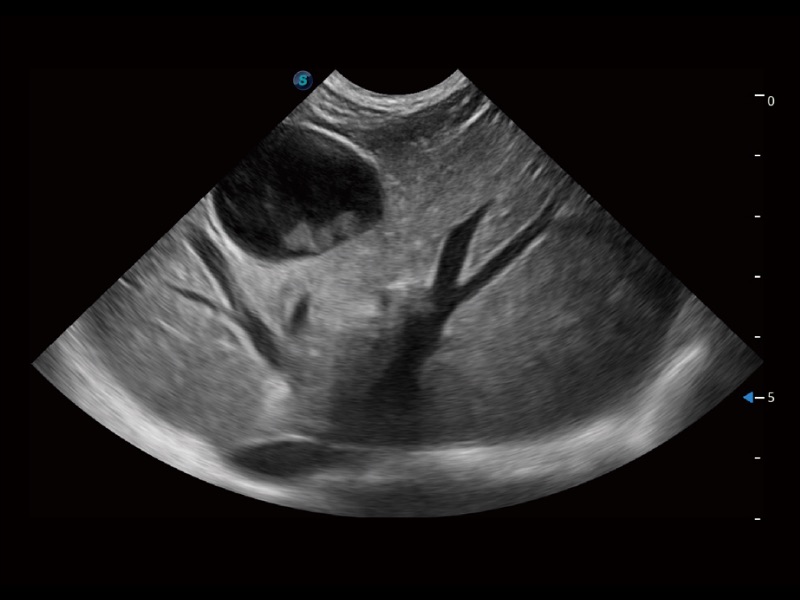

大型犬、马科、农场动物及大型异宠动物

ProPet 70专为动物医生设计,对不同的动物体型和生理结构作出了针对性的优化。通过动物影像专用软件,可满足个性化的应用需求,帮助动物医生获得更精确的诊断数据。

ProPet 70 全新的动物超声智能软件和丰富的探头群,为动物医生提供了高清晰度和精细分辨率的图像,无论在宠物、马科、畜牧还是实验室动物等应用中都可以轻松应对,为您的日常工作带来满意的体验。